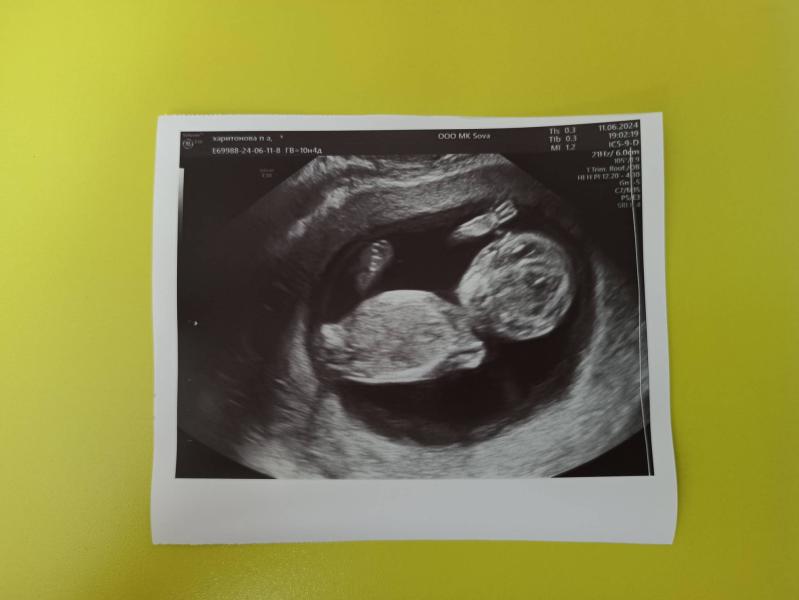

Вчера состоялась наша незапланированная встреча с малышом🥺 лежит, кайфует, рукой машет. Врач очень понравилась, делала в сове, все посмотрела, сказала развиваемся как надо, отклонений не видит🤭

Анализ на пол до сих пор ждем, сдала 6 июня, надеюсь, что скоро придёт 🤞 а пока подумайте, кто это может быть? Какие предположения?)

П. С. Я знаю, что по фото не определить, но, кстати, сама очень часто угадывала, когда девушки спрашивали пол🤭